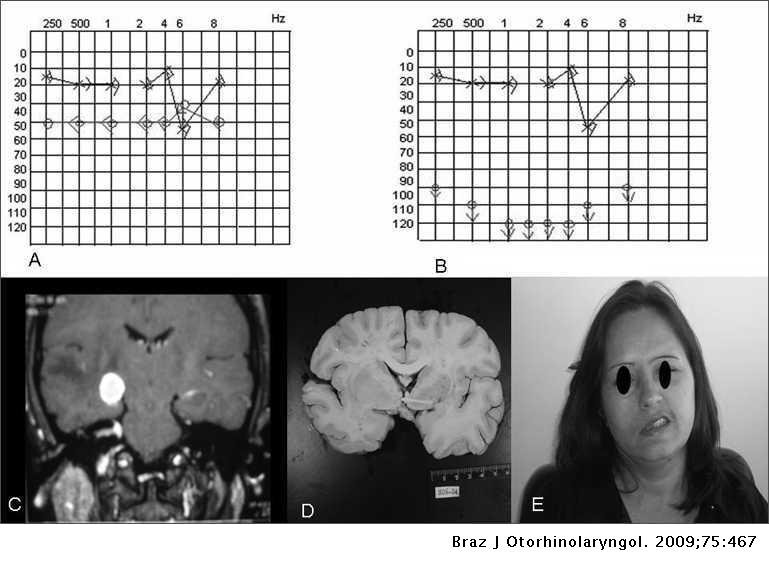

Lil Nas X Hospitalized: Facial Paralysis Sparks Concern

Lil Nas X Hospitalized After Experiencing Facial Paralysis Grammy-winning artist Lil Nas X is hospi...